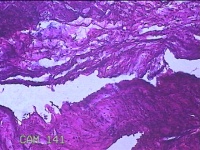

右侧卵巢囊肿

性别

女

年龄

19岁

临床诊断

一般病史

下腹痛1小时。

标本名称

大体所见

灰白暗红色囊壁样组织11x4.5x2.3cm两块,表面糜烂,因已切开,囊内容物已流失,囊壁厚0.1cm。